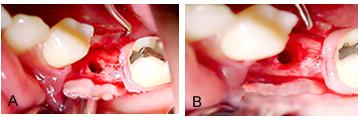

Figuras 2 a, b e c.

Figura 2a, mostra a cavidade óssea após a remoção do dente, evidenciando a grande perda óssea na área.

Figura 2 b, mostra o material de preenchimento que foi utilizado, Hidroxiapatita (Gen-phos) mais osso cortical e medular liofilizado (Gen-tech, Genius da Baumer), misturado com Colagel.

Figura 2 c, mostra o alvéolo refeito com material de reenchimento, onde será colocada uma membrana Intra-lock, para sutura dos retalhos.

Figuras 3 a, b e c.

Figura 3a, Raízes extraídas com o núcleo.

Figura 3b, sutura da ferida cirúrgica, procurando deixar a membrana reabsorvível bem fixada e os retalhos unidos de forma a propiciar uma cicatrização em primeira intenção, da mucosa gengival.

Figura 3c, a cicatrização da ferida cirúrgica, 30 dias após a extração e ROG.